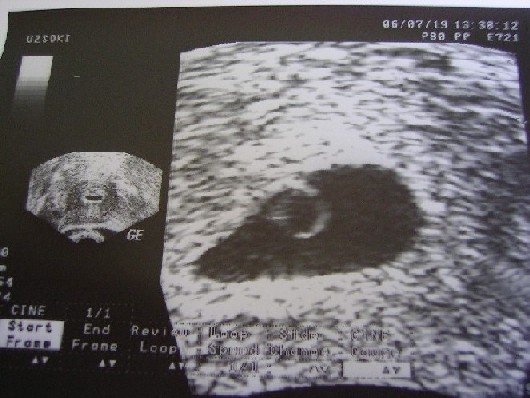

Olvastam a történetedet, én szerintem olyan még nem volt, hogy valaki megbánta, hogy megtartotta a babáját, de az ellenkezője inkább. Mielőtt Zsuzsát megszültem, én is azt hittem magamról, hogy minden további nélkül elvetetnék egy nem kívánt terhességet. Lehet még gyermektelen állapotban meg is tettem volna, de most hogy Zsuzsa már van, és látom hogy az a kétcsíkos teszt varázslatosan egy kis személlyé fejlődött, most már nem tudnám megtenni, mert mindig az élne bennem, kinek a társaságáról mondanék le? Milyen baba/gyerek/ember lett volna az az absztrakt két csík a teszten?

Zsuzsa is véletlen baba volt abból a szempontból, hogy még védekeztünk, ő becsúszott. Nálunk is elég viharos volt a párkapcsolat, bennem is felmerült az elején az abortusz. De nem bántam meg, sőt... nem gondoltam volna, de most néha nagy szívfájdalmat okozok magamnak azzal, hogy belegondolok, most nem lenne Zsuzsám, ha akkor úgy döntöttem volna. Páromból nagyon jó apuka és nagyon jó társ lett. A tenyerén hord, főleg mikor terhes vagyok, és mikor nem, akkor is keményen dolgozik hogy stabil maradjon. Sajnos ő egy eléggé instabil személyiség és néha felborul az egyensúlya, de azt kell hogy mondjam, hogy egyre ritkábban, mióta család vagyunk. És remélem miután négyen leszünk, még ritkábban fog ez megtörténni.